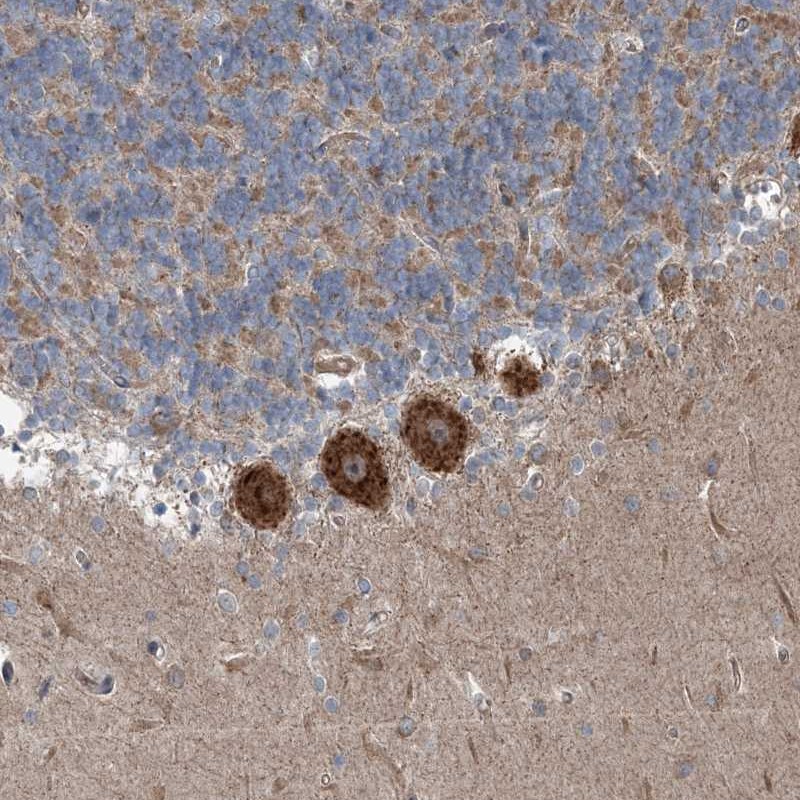

Immunohistochemical staining of human cerebellum shows strong cytoplasmic positivity in purkinje cells.